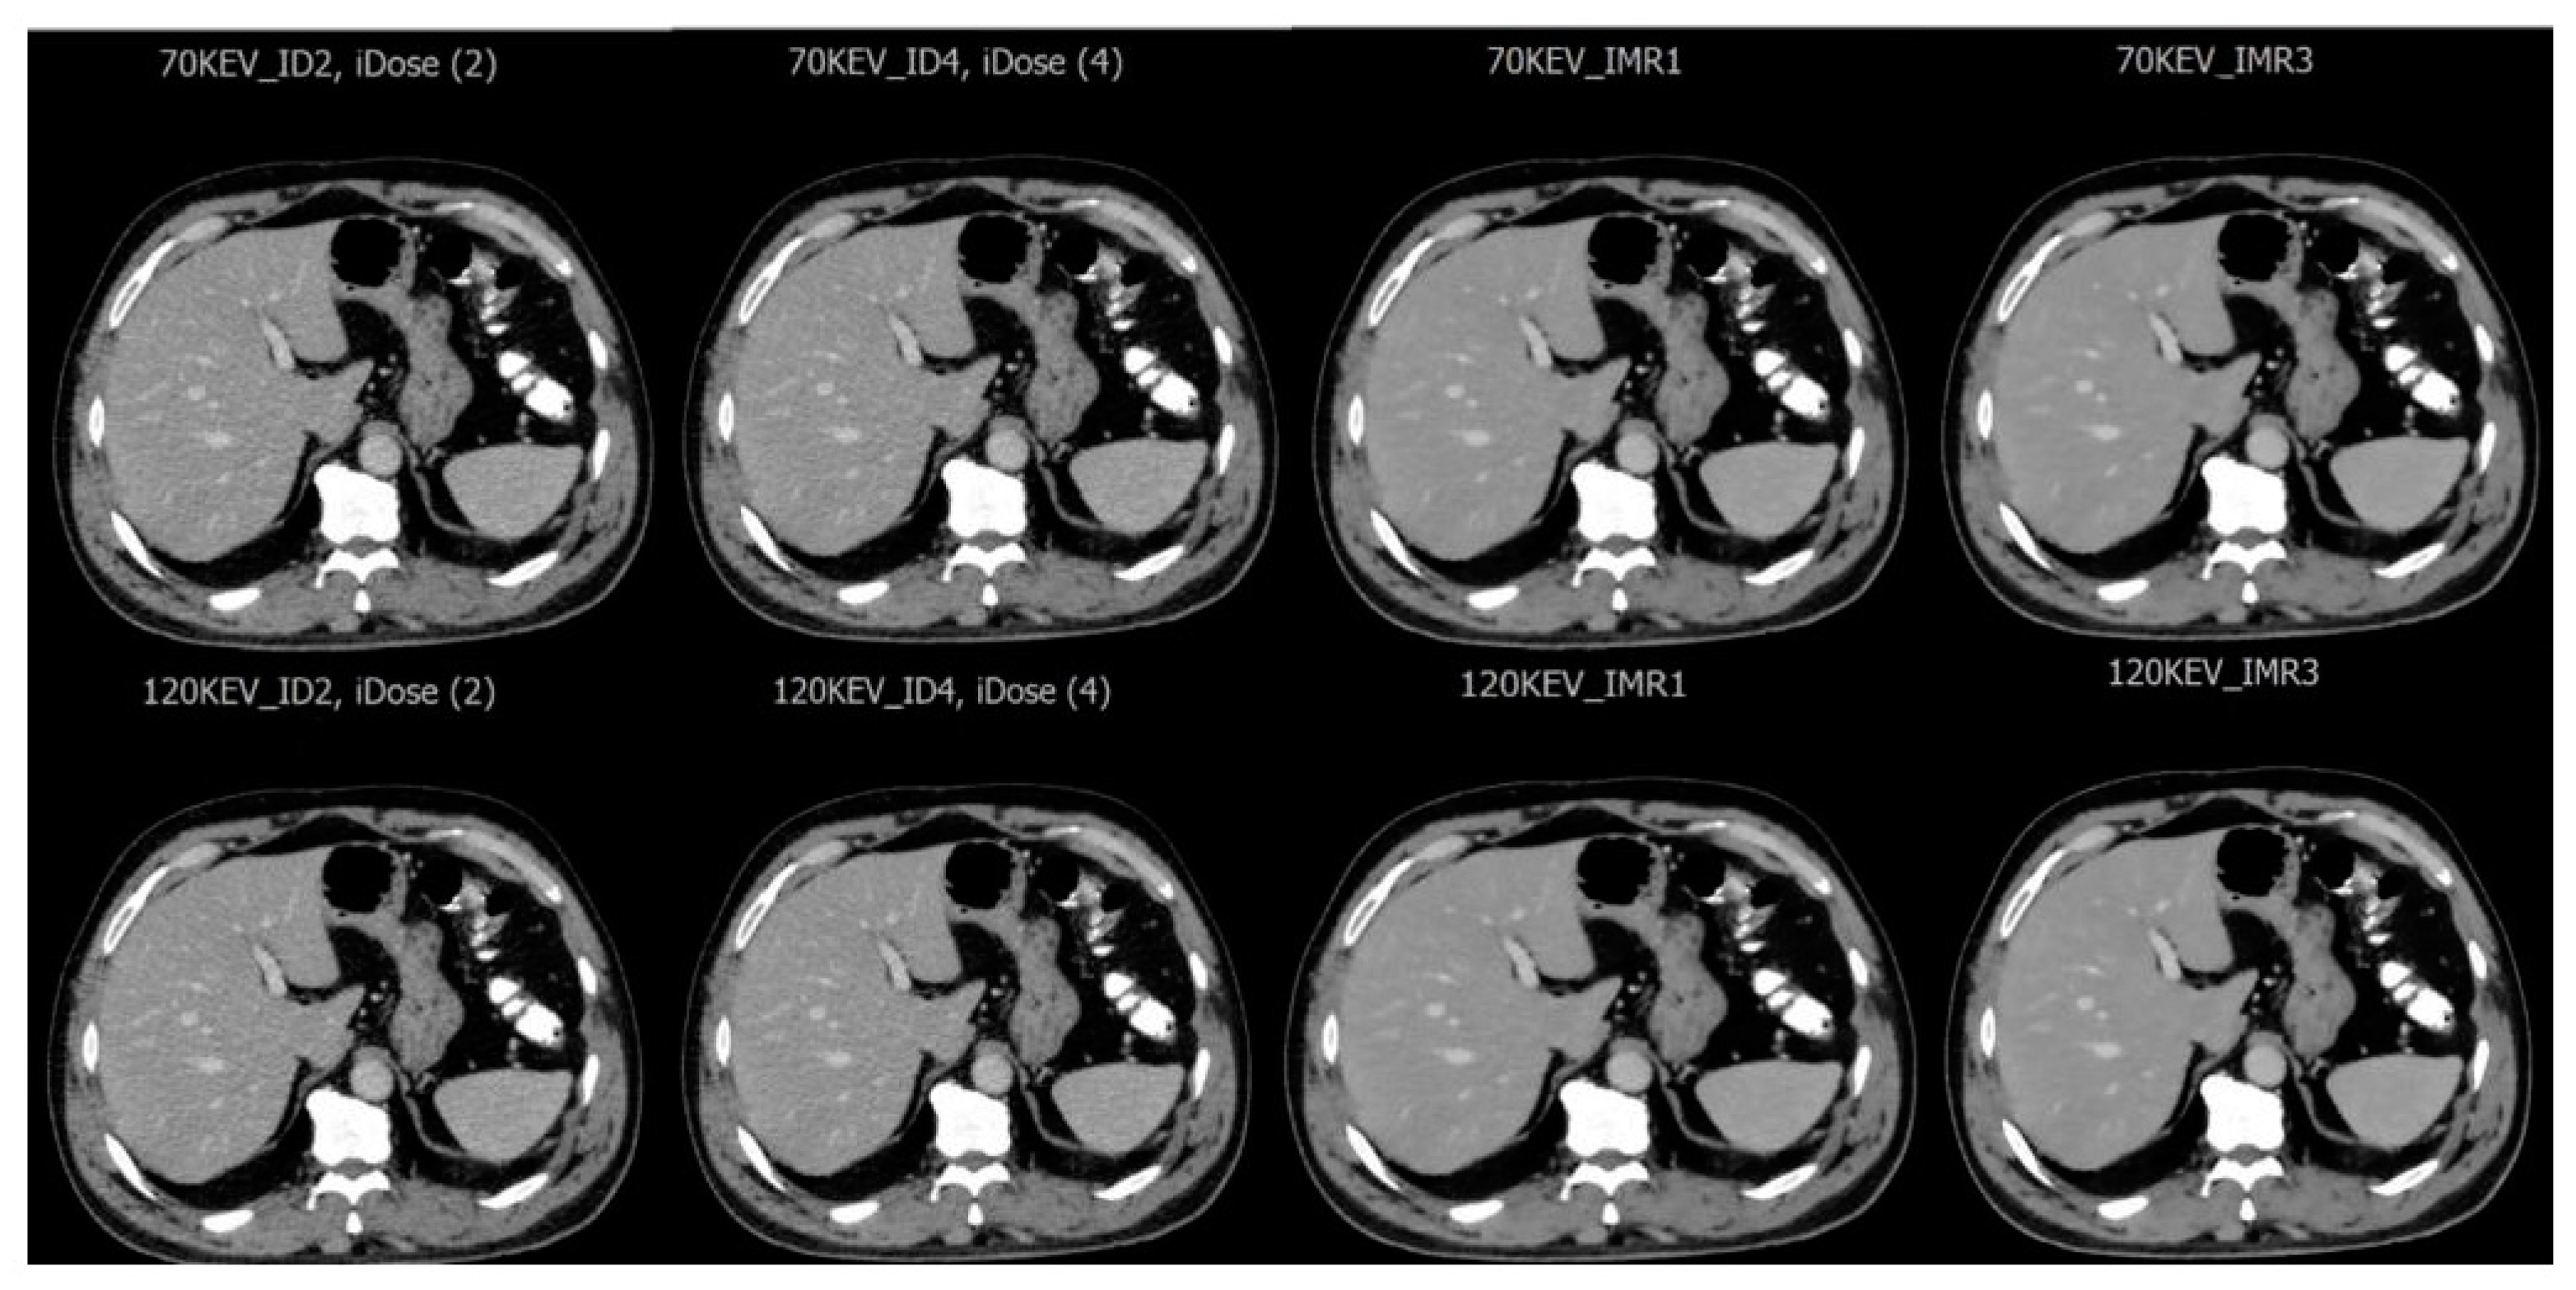

3.1. Imaging Assessment of Metastatic and Hemangioma Cases

| Reconstruction Techniques | iDose | IMR |

| Reconstructed image output | iDose2 70 keV | IMR1 70 keV |

| iDose2 120 keV | IMR1 120 keV | |

| iDose4 70 keV | IMR3 70 keV | |

| iDose4 120 keV | IMR3 120 keV |